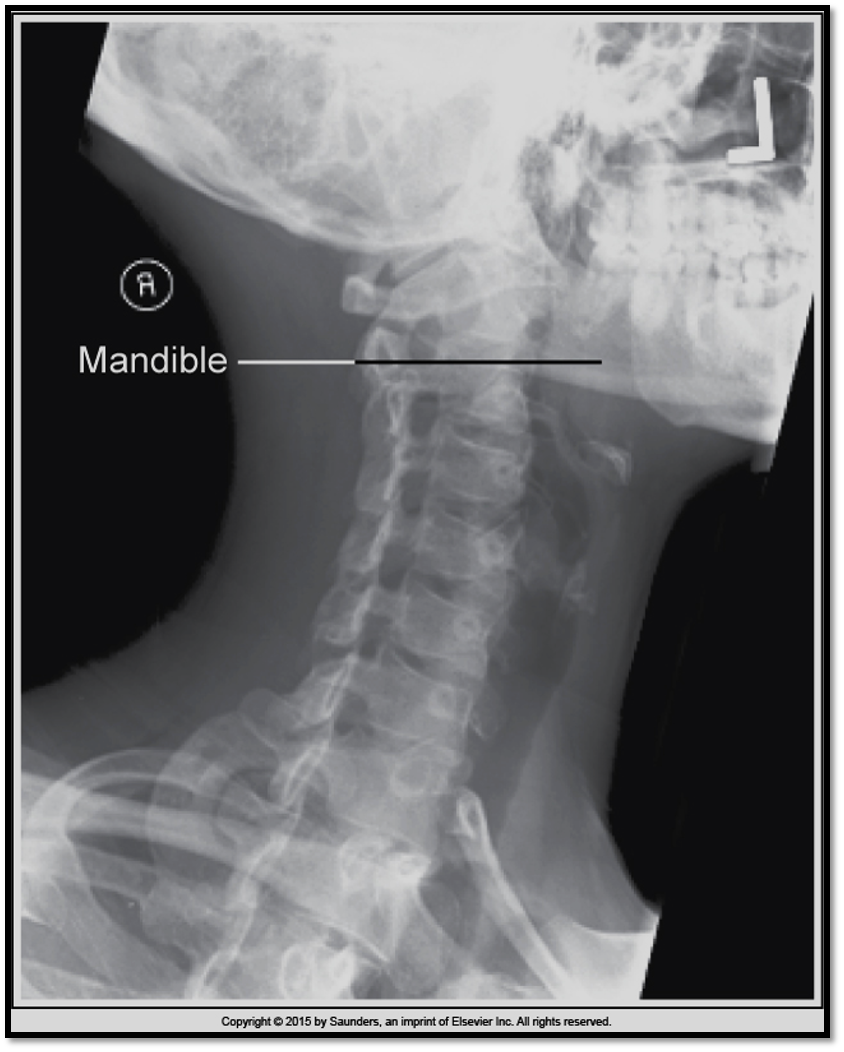

Lateral Cspine Criteria

• SI’d articular pillars and open zygopophyseal joints

• superimposition of posterior vertebral bodies

• mandible off spine

• open intervertebral spaces